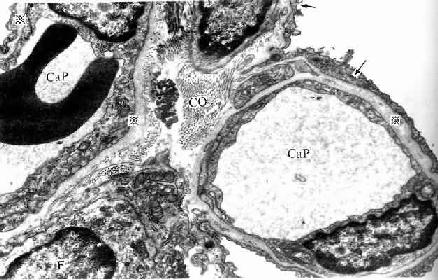

(2)肺泡隔( alveolar septum):相邻肺泡之间的薄层结缔组织构成肺泡隔,属肺的间质。肺泡隔内含密集的毛细血管网,毛细血管为连续型,内皮甚薄,无孔,胞质内含较多吞饮小泡。隔的厚薄不一,弹性纤维较丰富,也有少量胶原纤维和网状纤维,并有成纤维细胞、巨噬细胞、浆细胞和肥大细胞等以及淋巴管和神经纤维。隔内丰富的弹性纤维有助于保持肺泡的弹性,老年人弹性纤维退化,炎症等病变也可破坏弹性纤维,使肺泡弹性减弱,肺泡渐扩大,导致肺气肿,肺换气功能减低。隔内的毛细血管大多紧贴肺泡上皮,上皮基膜与内皮基膜相互融合;有的部位的肺泡上皮与毛细管内有少量结缔组织(图14-15)。

图14-15 人肺泡隔电镜像 ×13500

Cap毛细血管,F成纤维细胞,

CO胶原原纤维,※基膜,↑Ⅰ型肺泡细胞

(4)气血屏障(blood-air barrier):肺泡内气体与血液内气体分子交换所通过的结构称气血屏障。它由以下结构组成:肺泡表面液体层、Ⅰ型肺泡细胞与基膜、薄层结缔组织、毛细血管基膜与内皮。有的部位的肺泡上皮与血管内皮之间无结缔组织,两层基膜直接相贴而融合(图14-15)。气血屏障很薄,总厚度约0.5μm。间质性肺炎时,肺泡隔结缔组织水肿,炎症细胞浸润,以致肺气体交换功能障碍。